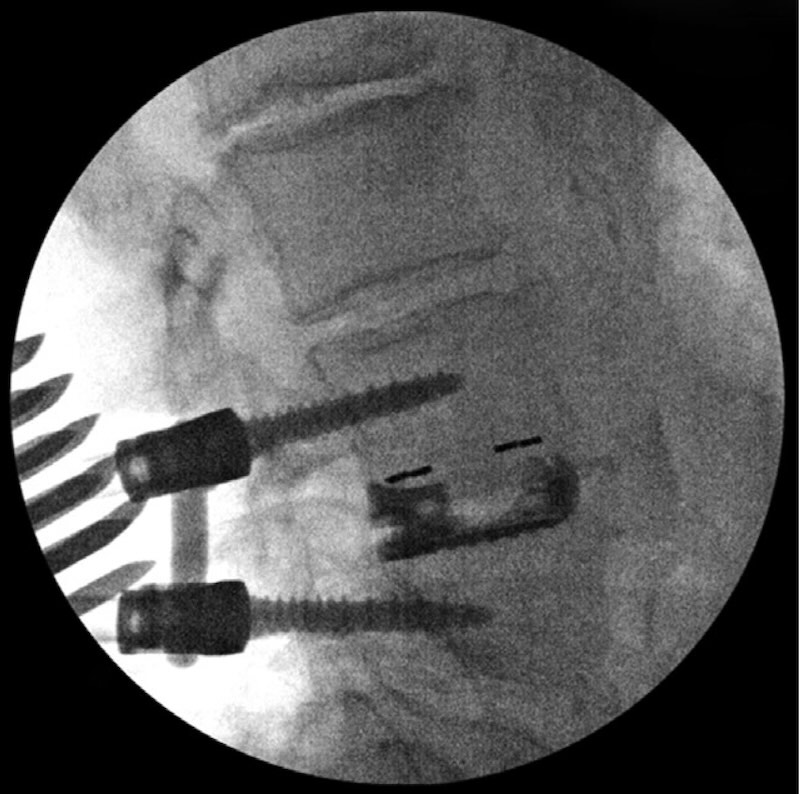

The Elevate Expandable lumbar interbody spacer by Medtronic. The expandable implant is made of a titanium base and a PEEK superior endplate for improved visualization.

• Titanium base with PEEK superior expandable

• 2 versions of implant:

• Standard implant: beings parallel and expands up to 8 degree lordosis with 1 mm posterior expansion and 4mm anterior

• Extra lordotic implant: no posterior height expansion with up to 13 degree lordosis